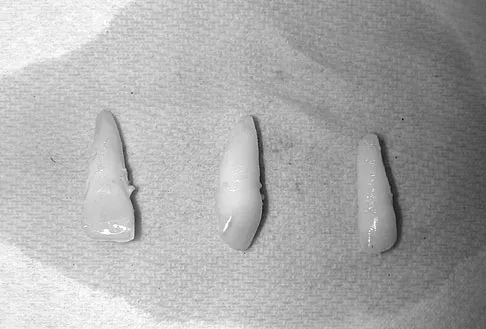

A 15-year-old female field hockey player sustains a blow to the mouth from a hockey stick. Three front teeth are knocked out and shown in Figure 4. In addition to calling a dentist immediately, what is the next best step in management?

Tooth avulsions can occur in contact or collision sports. An avulsed tooth is a medical emergency. The likelihood of survival of the tooth depends on the length of time that the tooth is out of the socket and the degree to which the periodontal ligament is damaged. The tooth should be handled only by the crown end and not the root end. It can be rinsed of debris with water or normal saline solution. The tooth should not be brushed or cleaned otherwise. During transport, the tooth must be kept moist. An avulsed tooth can be transported in whole milk, saliva, sterile saline solution, or commercially available kits with physiologic buffer solutions. The tooth and the athlete should be transported to the dentist for reinsertion as soon as possible and preferably within an hour. Krasner P: Management of sports-related tooth displacements and avulsions. Dent Clin North Am 2000;44:111-135. Sullivan JA, Anderson SJ (eds): Care of the Young Athlete. Rosemont IL, American Academy of Orthopaedic Surgeons, Elk Grove Village, IL, American Academy of Pediatrics, 2000, p 190.